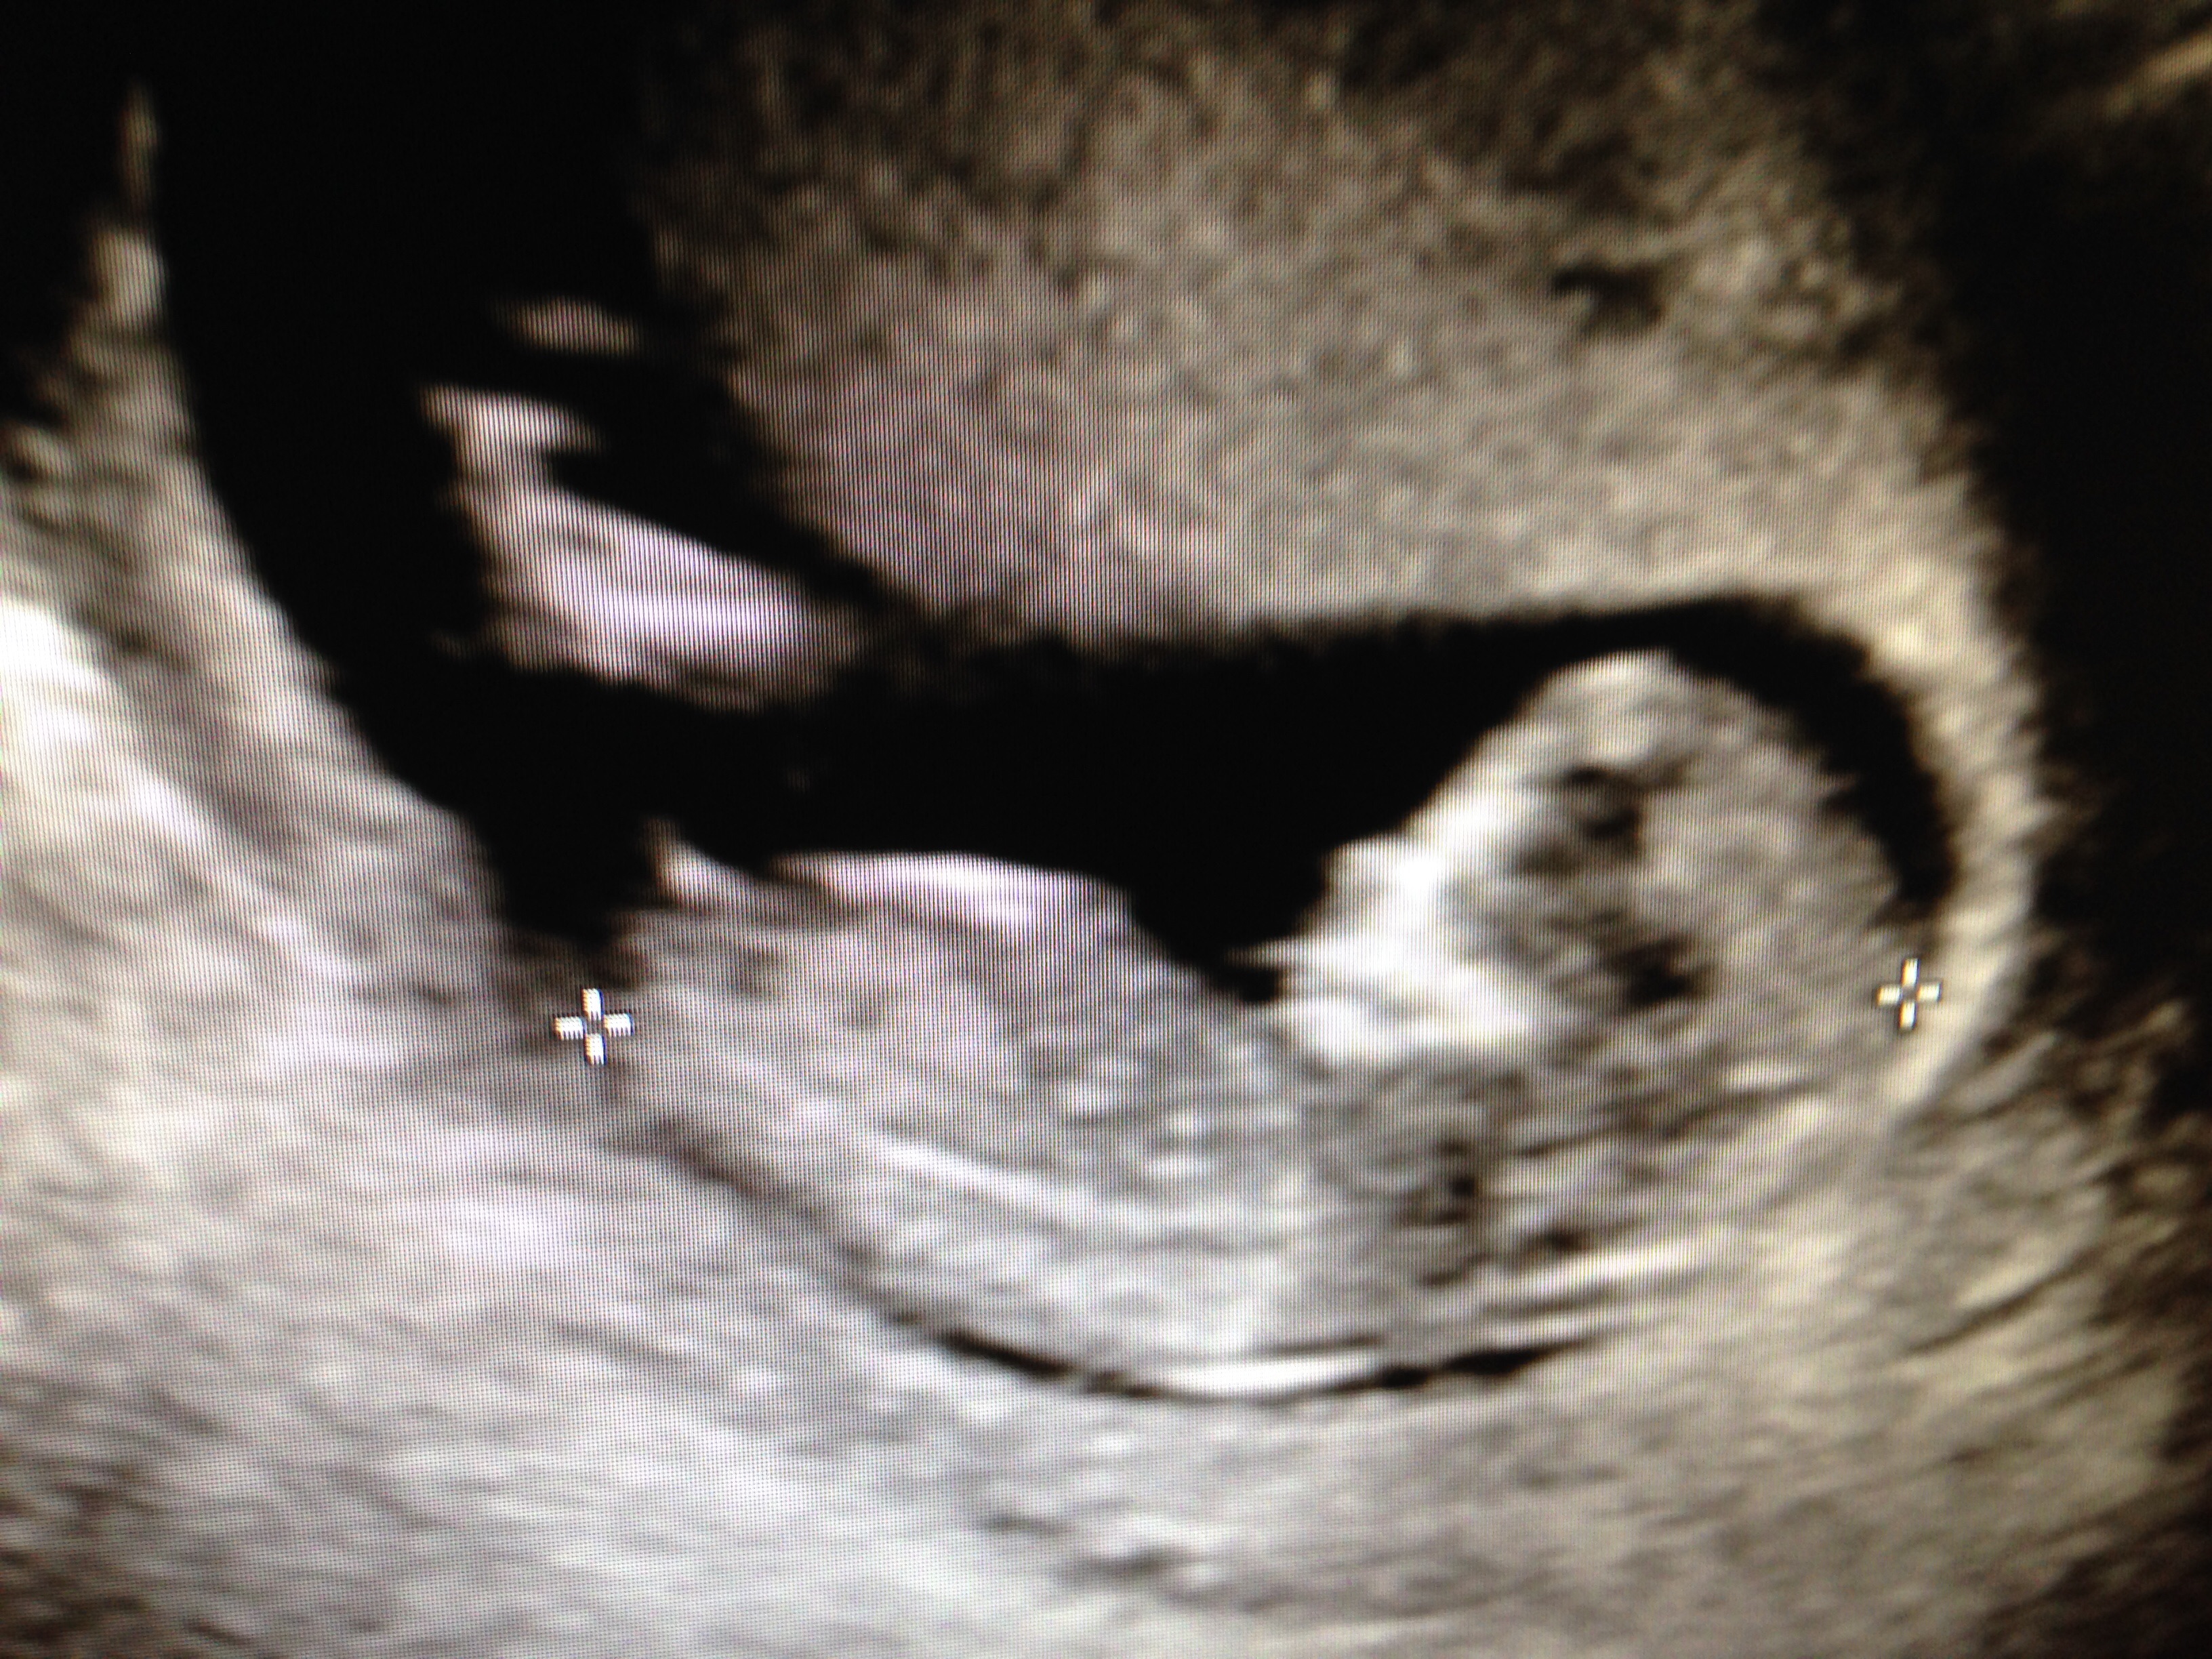

These were taken around 12 weeks

In the second photo---is that the nub pointing up ? Or no because it's usually not before the legs ?

I would say no, I'm not seeing a nub in either picture. Sorry.

Do have anymore pics? Not confident guessing on these, but very slight boy lean if these are all you have. GL!

Thinking boy because it's early. Looks like it might be on the rise.